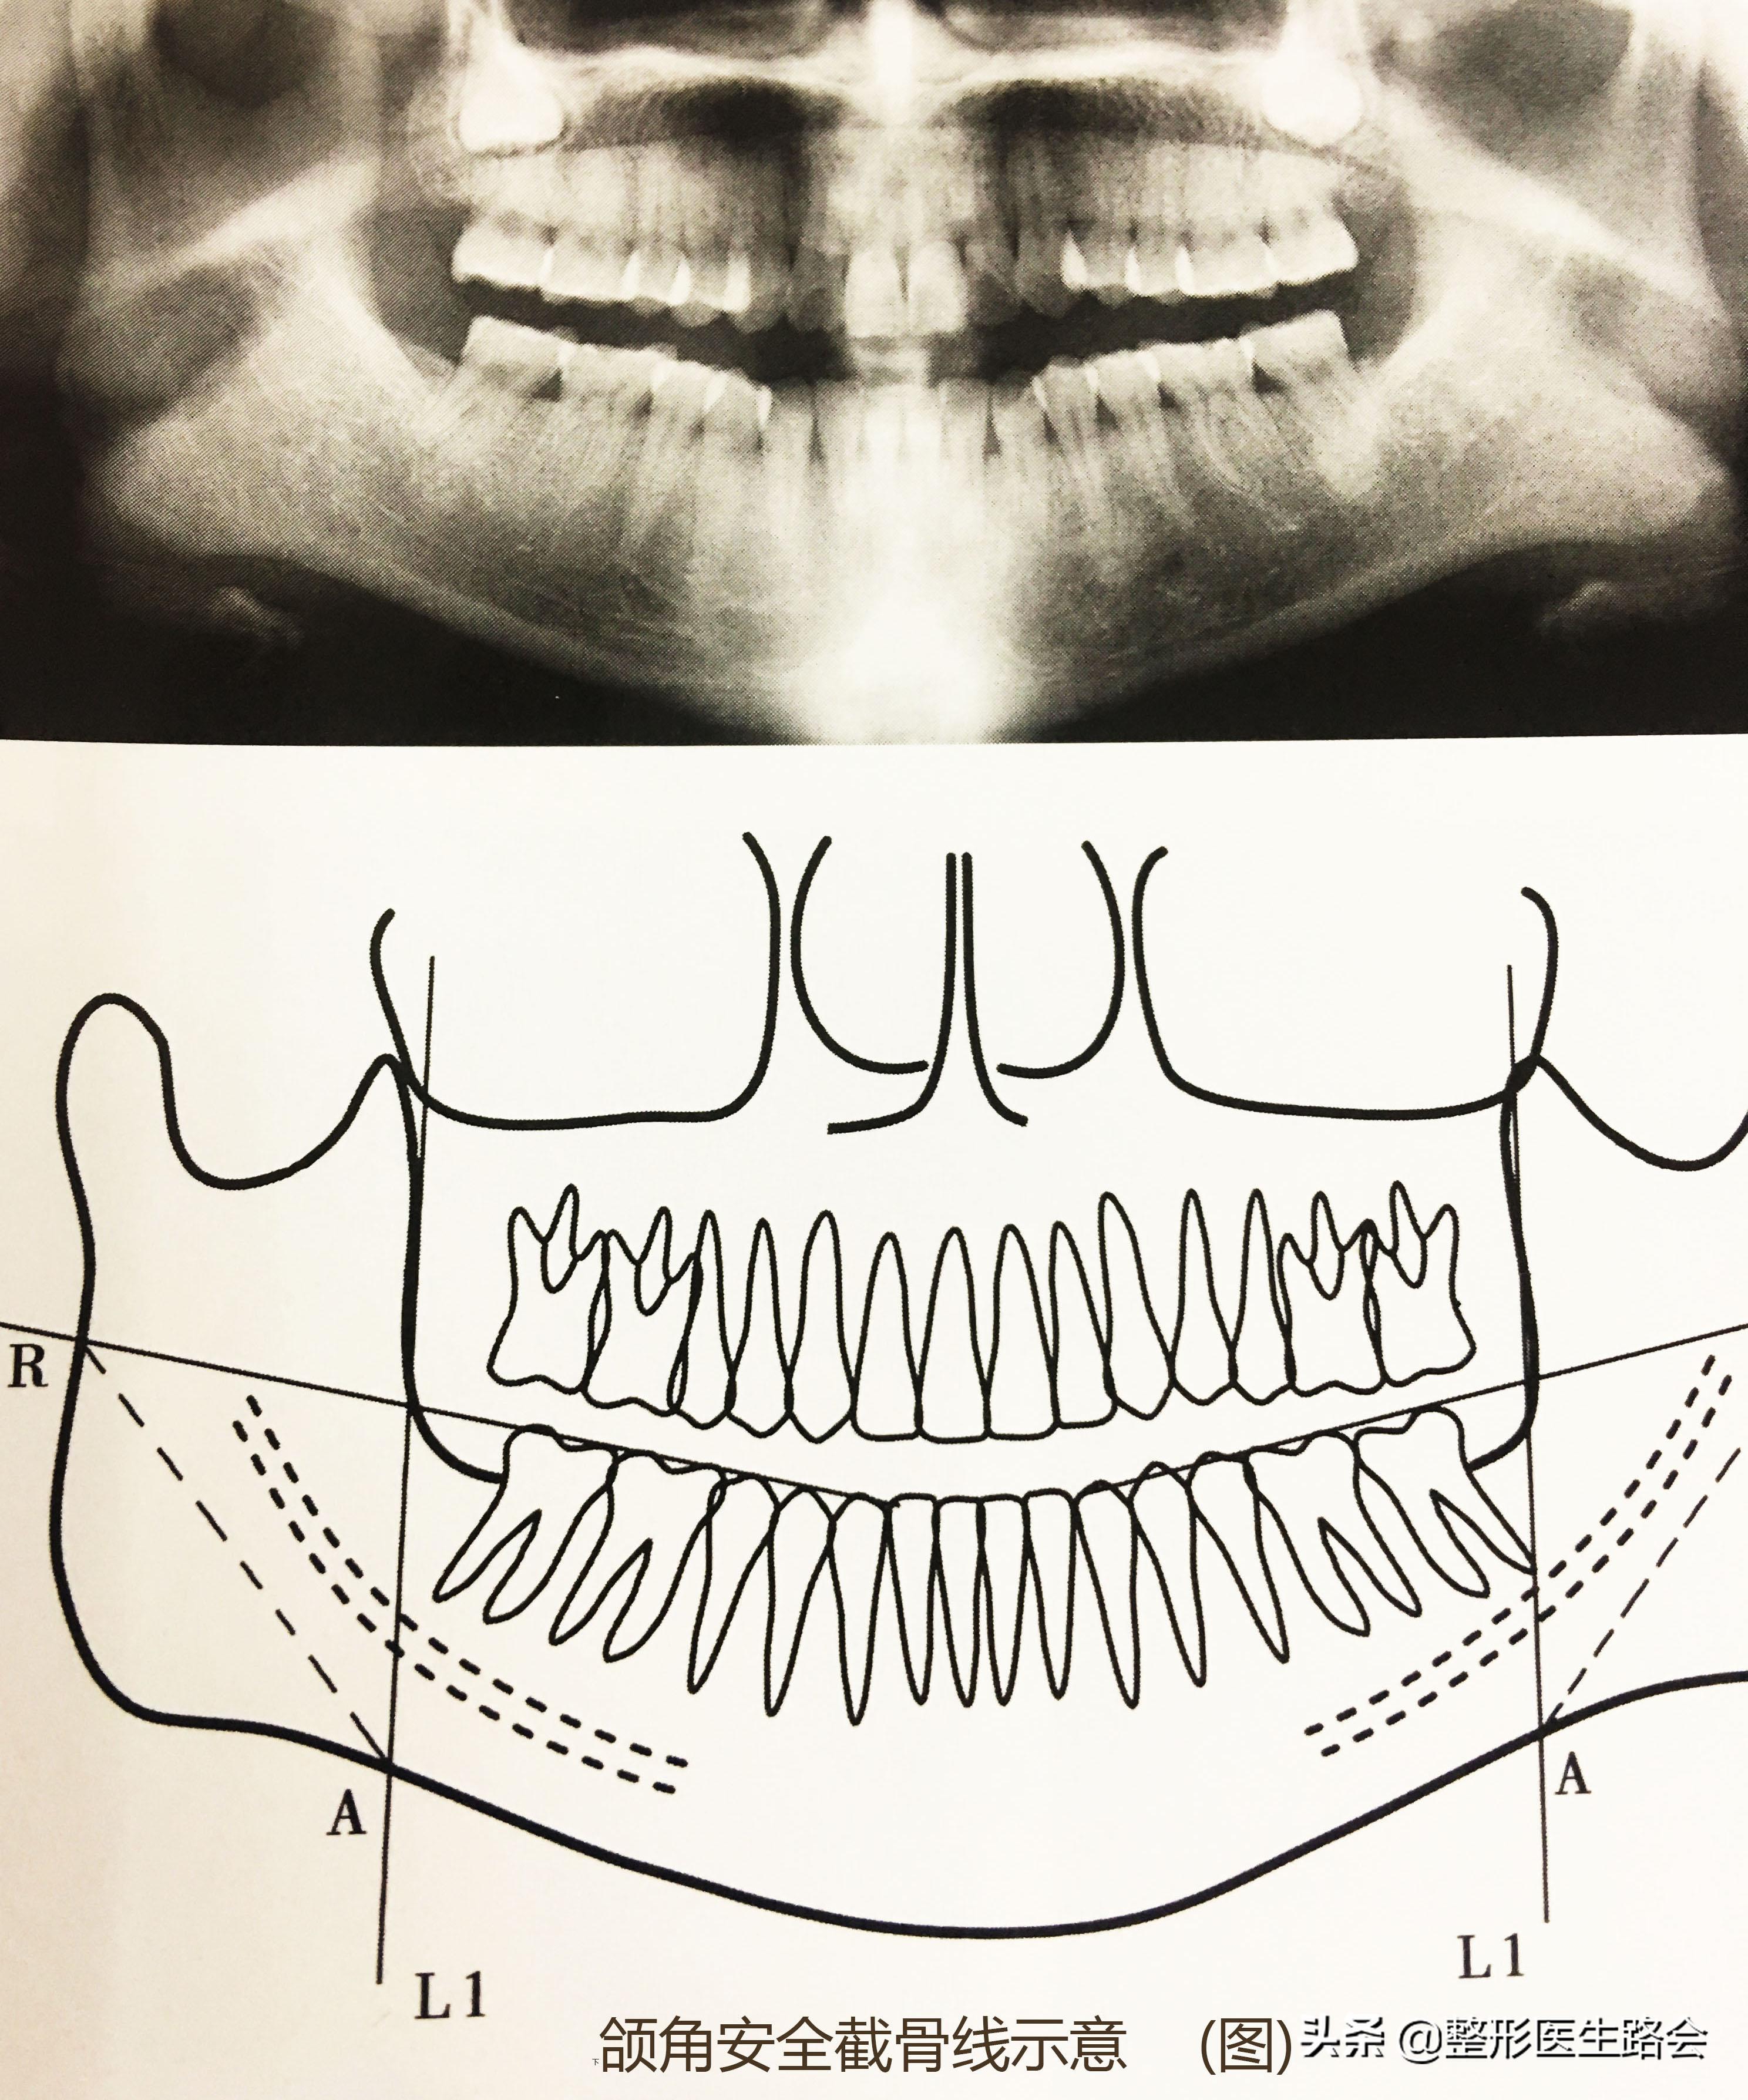

2. 根据设计的截骨量,画出截骨线;

安全截骨线

(补充:应该在距离下齿槽神经管下方5mm以上。向上,可能会造成手术器具对下齿槽神经产生损伤,过远,则可能远远达不到手术效果)